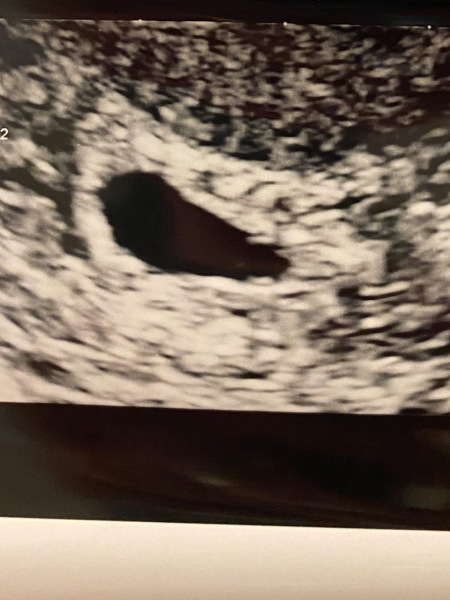

@Lemonbalm8 For reference this is my 5+2 scan with DD and you could only see the yolk sac, which is fine if you just want reassurance that baby is in the right place but if you want a chance of seeing the heartbeat you’re better off waiting closer to 7 weeks

BFP after recent loss